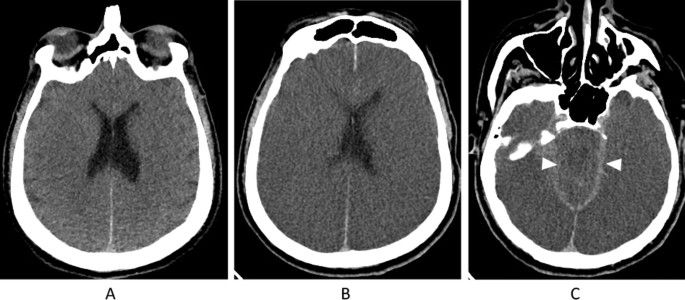

The initial non-contrast CT scan labeled as Image A, taken shortly after the patient experienced a cardiac arrest, revealed early signs of brain damage. This was indicated by the blurring of lines between the grey matter (the part of the brain responsible for processing information) and white matter (the parts that connect different brain regions), which should normally be distinct in the cerebral cortex.

The subsequent scans, labeled as Images B and C, conducted 36 hours later, showed an advancement of this condition. The blurring between grey and white matter now extended to include the brainstem, an area crucial for controlling vital life functions such as breathing and heart rate. Alongside this, there was a noticeable increase in cerebral edema, meaning the brain was swelling significantly. This swelling led to the pressing together and obliteration of the brain's folds (known as sulci) and the internal fluid chambers (ventricles), making them less visible. Also, the compression of the basilar cisterns, which are fluid-filled spaces at the brain's base, was observed. These changes, highlighted in the follow-up images B and C, illustrate the severe and widespread impact of the brain injury, helping to convey the gravity of the patient's situation in a more understandable way for those unfamiliar with medical terminology.